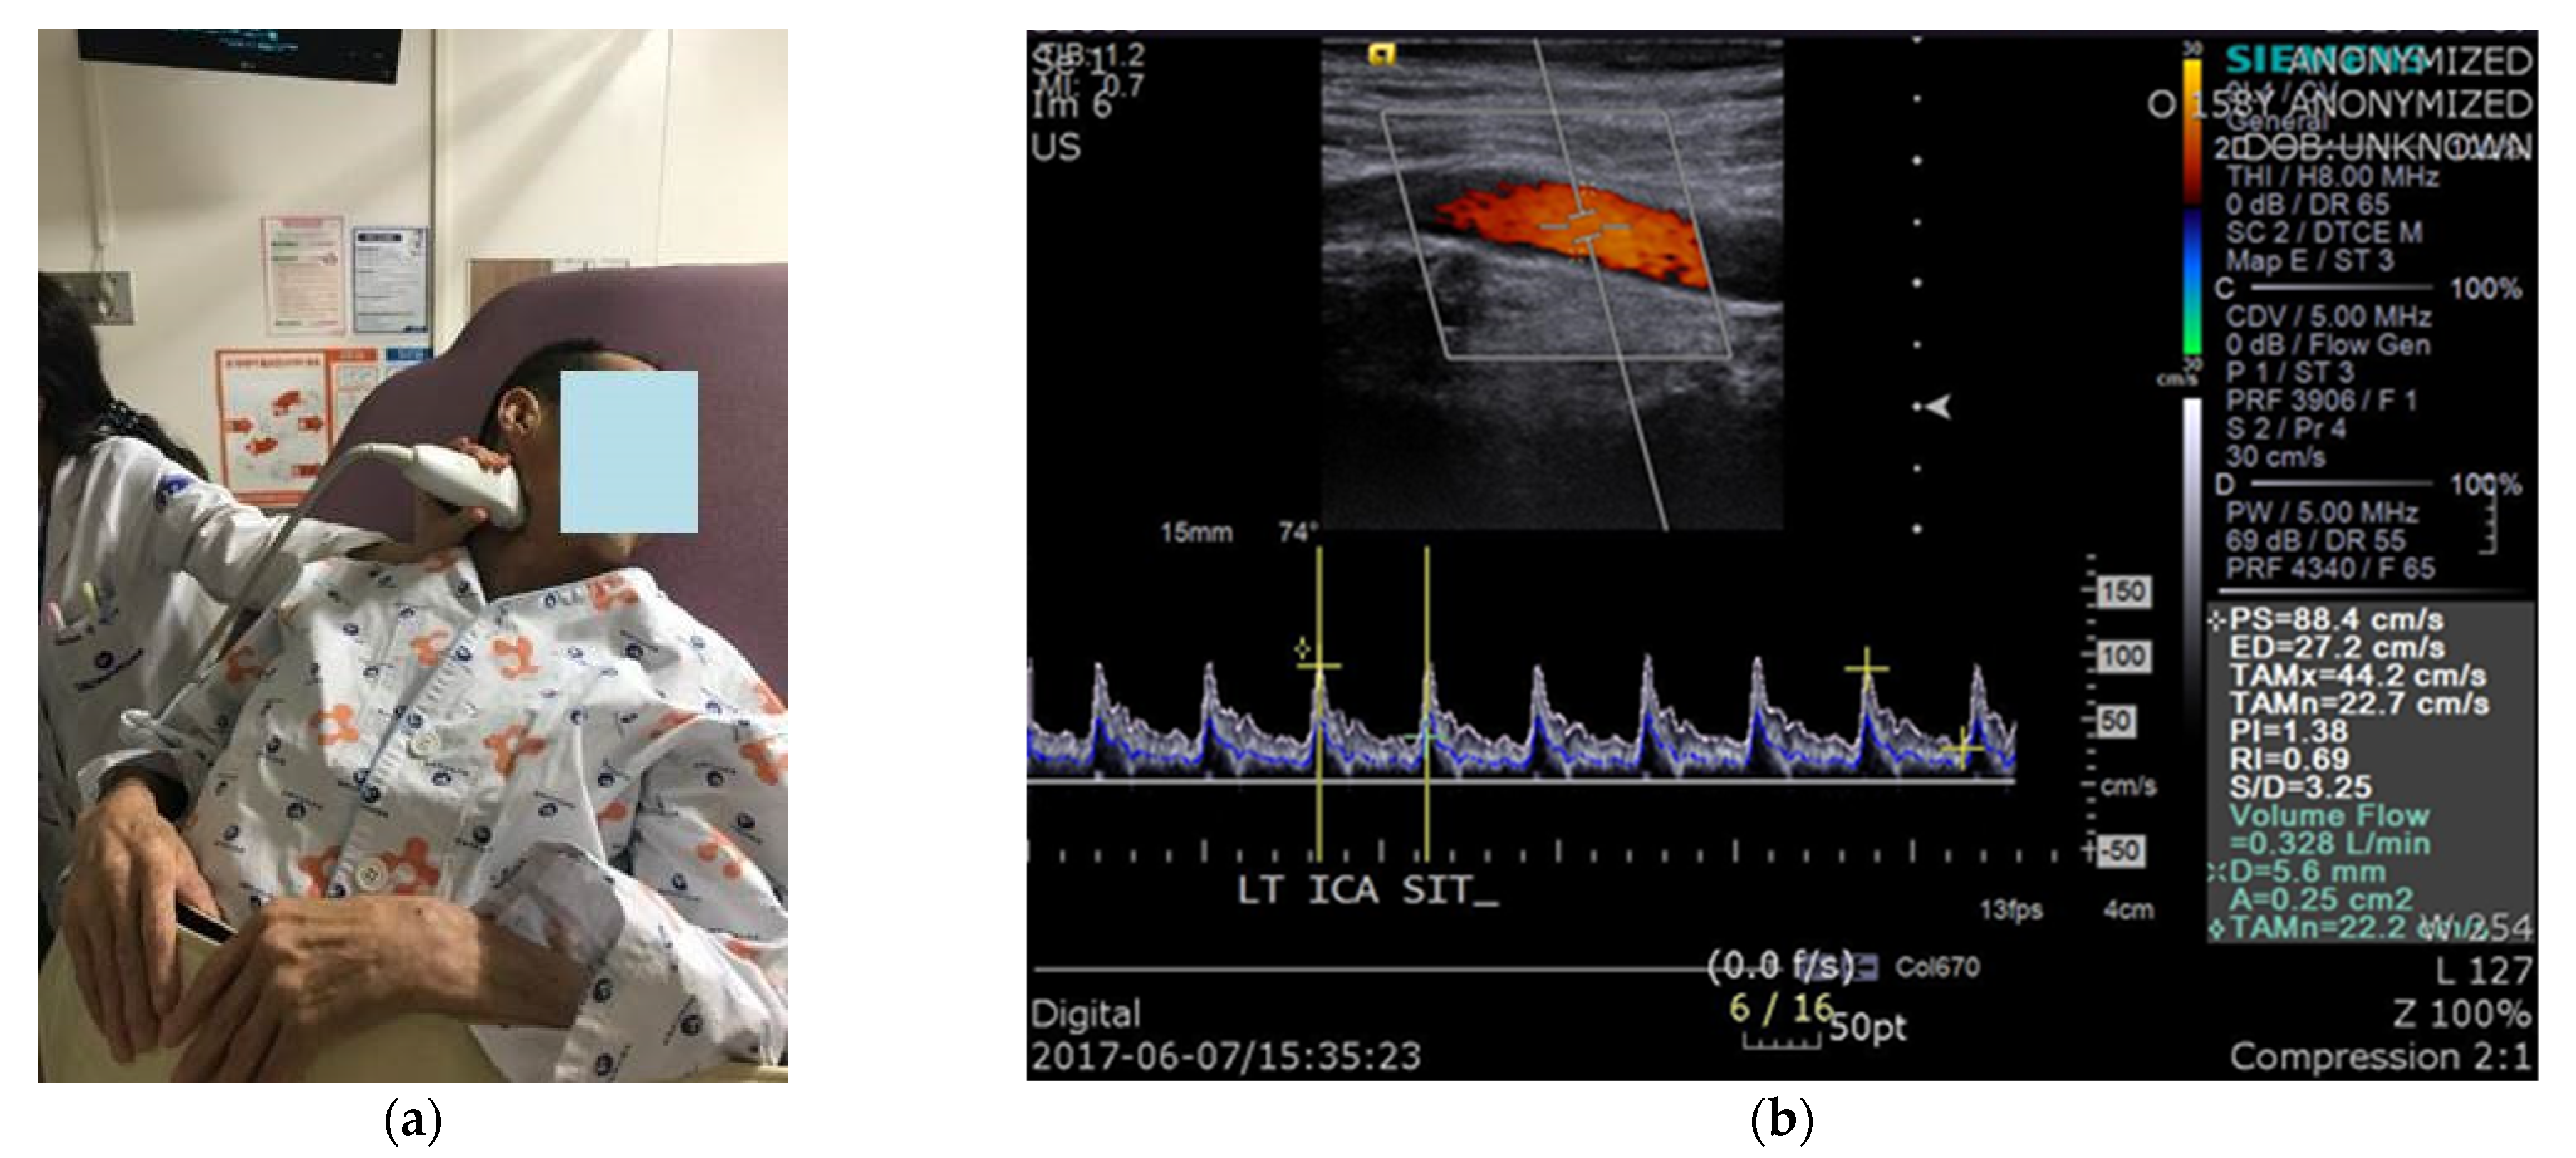

We conducted CDU during head-up tilt in patients with a CSCI. The ICA was studied on both sides, and intravascular flow volumes were calculated using a 9-MHz linear array transducer. BFV measurements were automatically calculated by the built-in software of the ultrasound device (Siemens ACUSON, Siemens Healthcare, Erlangen, Germany). For flow-volume measurements, the head was turned 25°–40° to the contralateral side, and a straight segment of the ICA, at least 2 cm above the carotid bulb, was selected (Figure 1). Measurements were performed on a horizontal segment in the sagittal plane. The arterial diameter was calculated as a vertical line through the lumen between the echogenic intimal layers. The value obtained from the test is volume flow rate, which was automatically calculated from the cross-sectional area of the blood vessel and the time-averaged mean velocity: volume flow rate = area (cm2) × time-averaged mean velocity (cm/s). The peak systolic velocity, end diastolic velocity, time-averaged mean velocity, vessel diameter, and vessel area were all measured during the test. All patients were allowed to rest on the examination table for 5 min before the test. CBFV, BP, and heart rate (HR) were measured in the supine position, immediately after the patient was tilted by 50°, and 5 min after the tilt. To increase the reliability of the test, CBF was measured three times in each position, and the mean value was used. In addition, the presence or absence of presyncopal symptoms, such as dizziness, light-headedness, nausea, and blurry vision, in each position, was recorded.

Figure 1.

Carotid duplex sonography: (a) The position of the patient and measurements of cerebral blood flow using carotid duplex ultrasonography; (b) The value of interest in the test was volume flow.